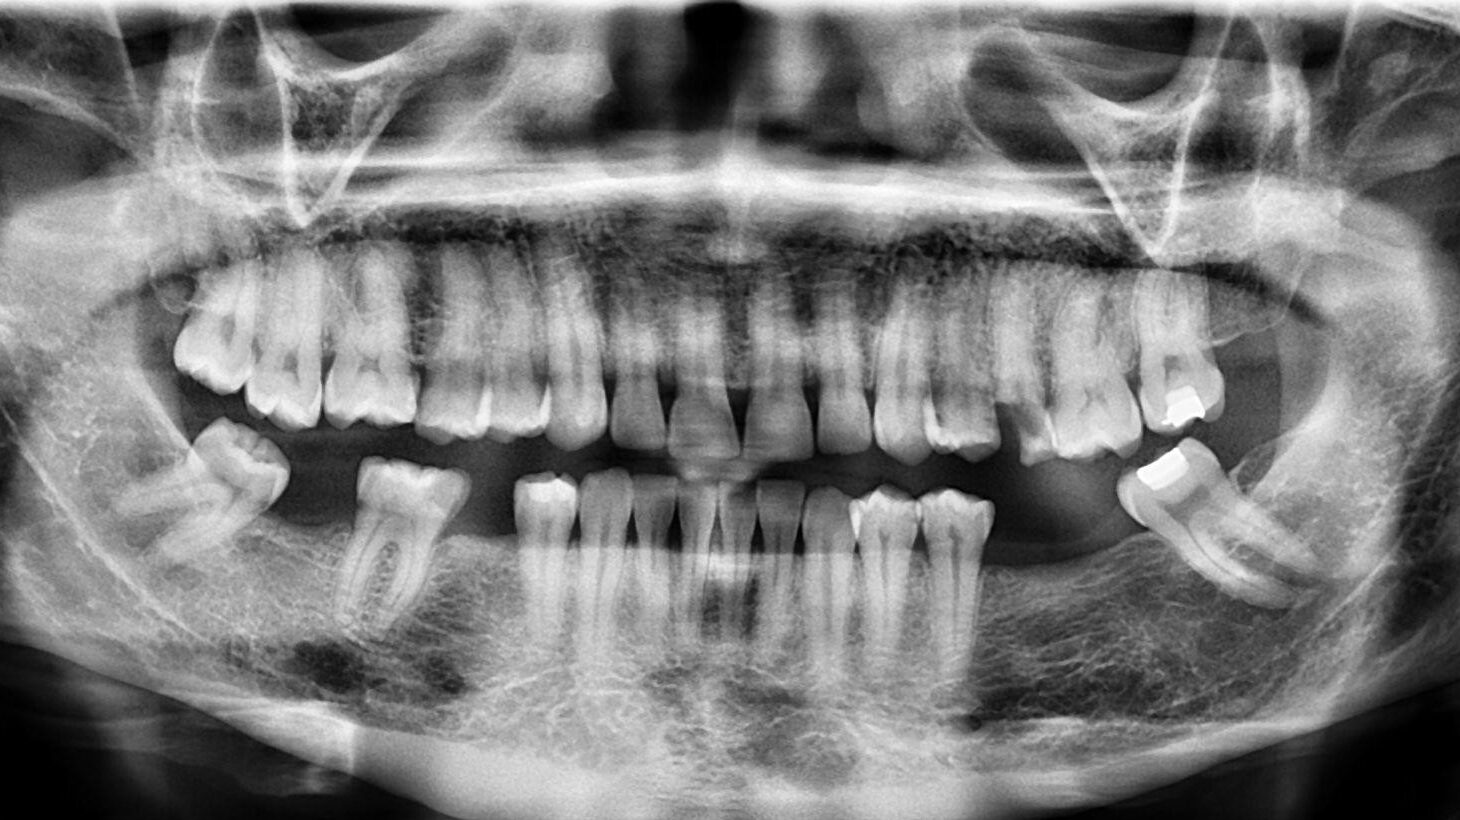

9. What option cannot be selected for this panoramic X ray?

10 / 23